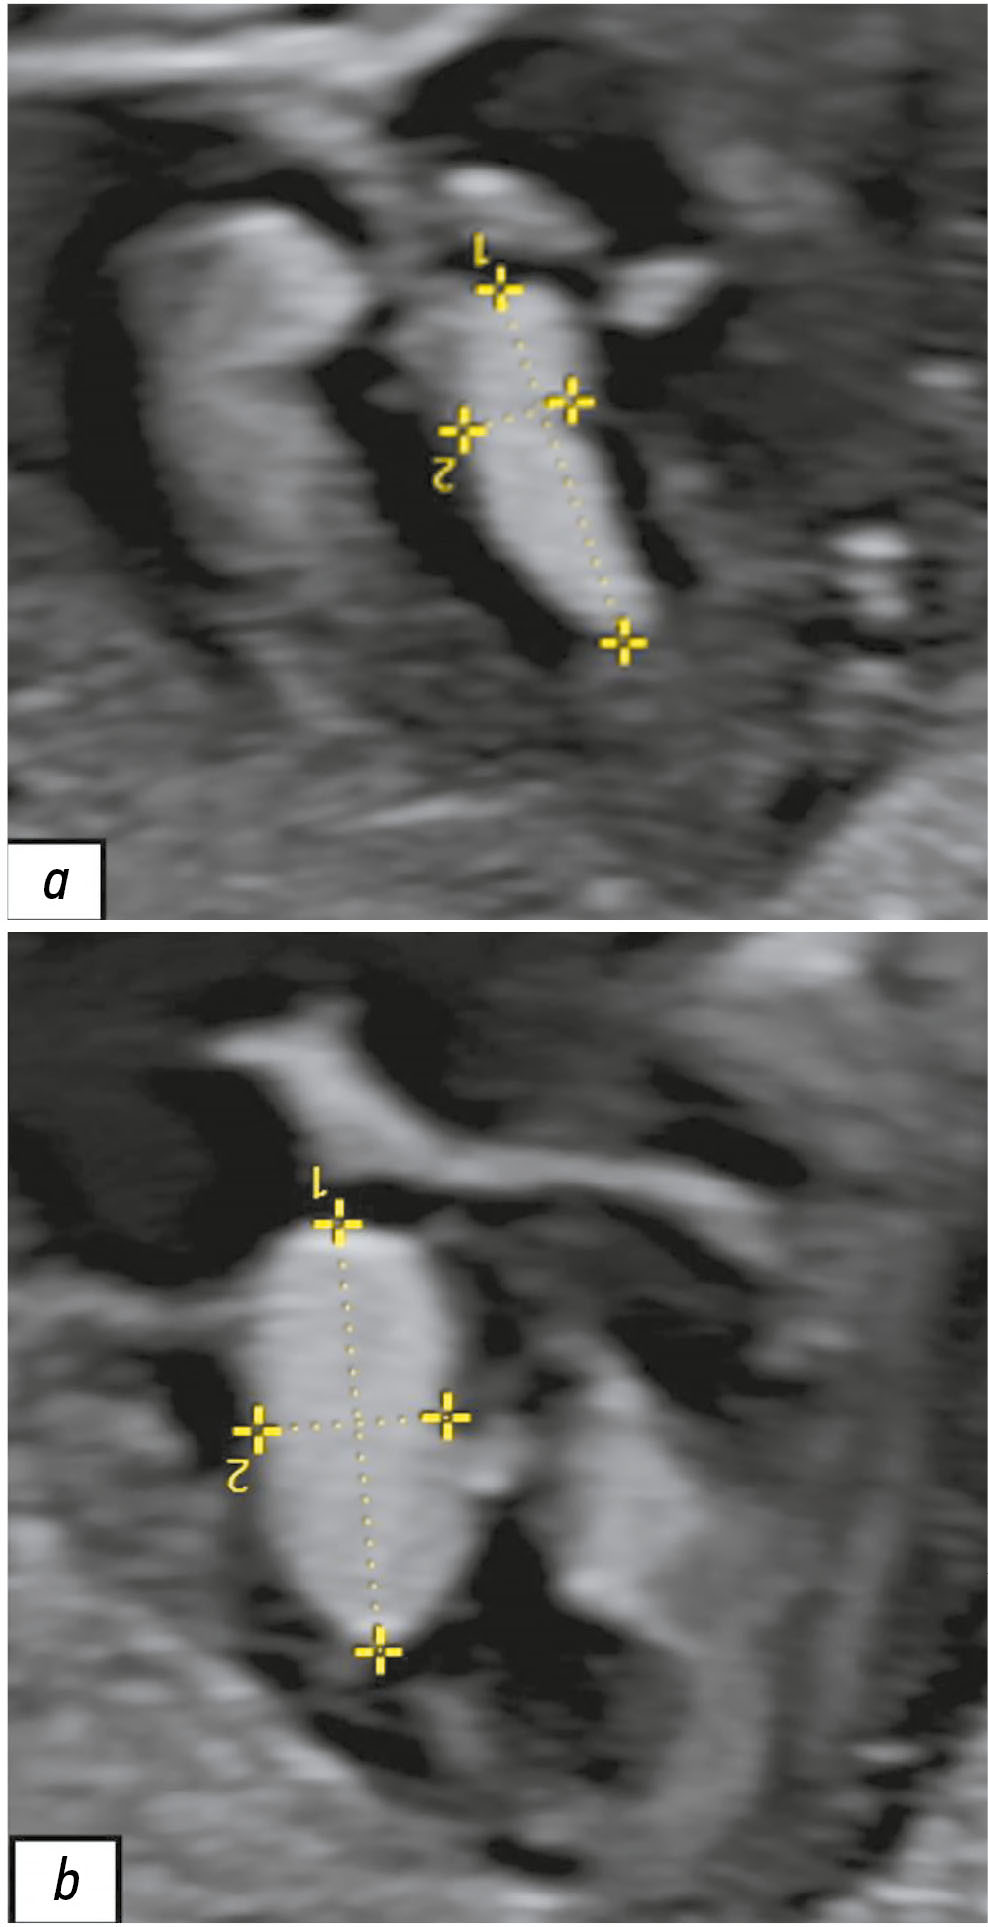

磁共振成像在孕期诊断结节性硬化症中的应用:临床案例

早期识别罕见病患者,如结节性硬化症,需要集体协作并引入新的孕期诊断方法,不仅依赖于超声检查,还应使用磁共振成像。关于Bourneville-Pringle病的临床表现的知识积累,以及诊断方法的改进,使得该疾病的早期发现成为可能。通过磁共振成像,能够获得高质量的大脑解剖和功能性图像,且可在不同的扫描平面上进行观察,从而显著提高该方法在早期(孕期)诊断结节性硬化症脑部表现的灵敏度和信息量。此外,进行磁共振成像还可以识别纵隔的肿块。这一事实表明,采用磁共振成像作为主要诊断手段,对结节性硬化症的诊断应采取综合性方法,评估胎儿心血管系统和中枢神经系统的状态。本文展示了一个孕期诊断结节性硬化症的临床案例,随后对新生儿进行了检查并进行了基因诊断验证。此案例的展示验证了磁共振成像在孕期诊断结节性硬化症中的诊断重要性。